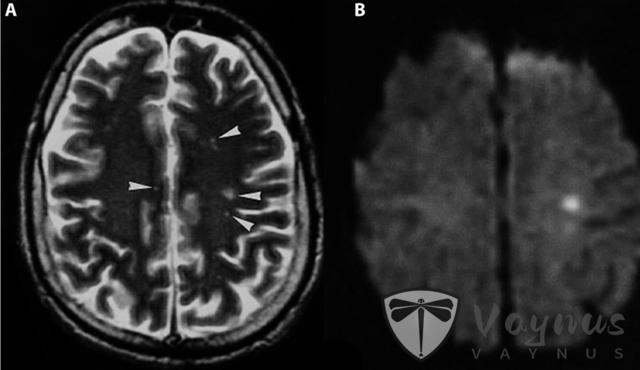

尼帕病毒感染后脑炎的核磁共振图像